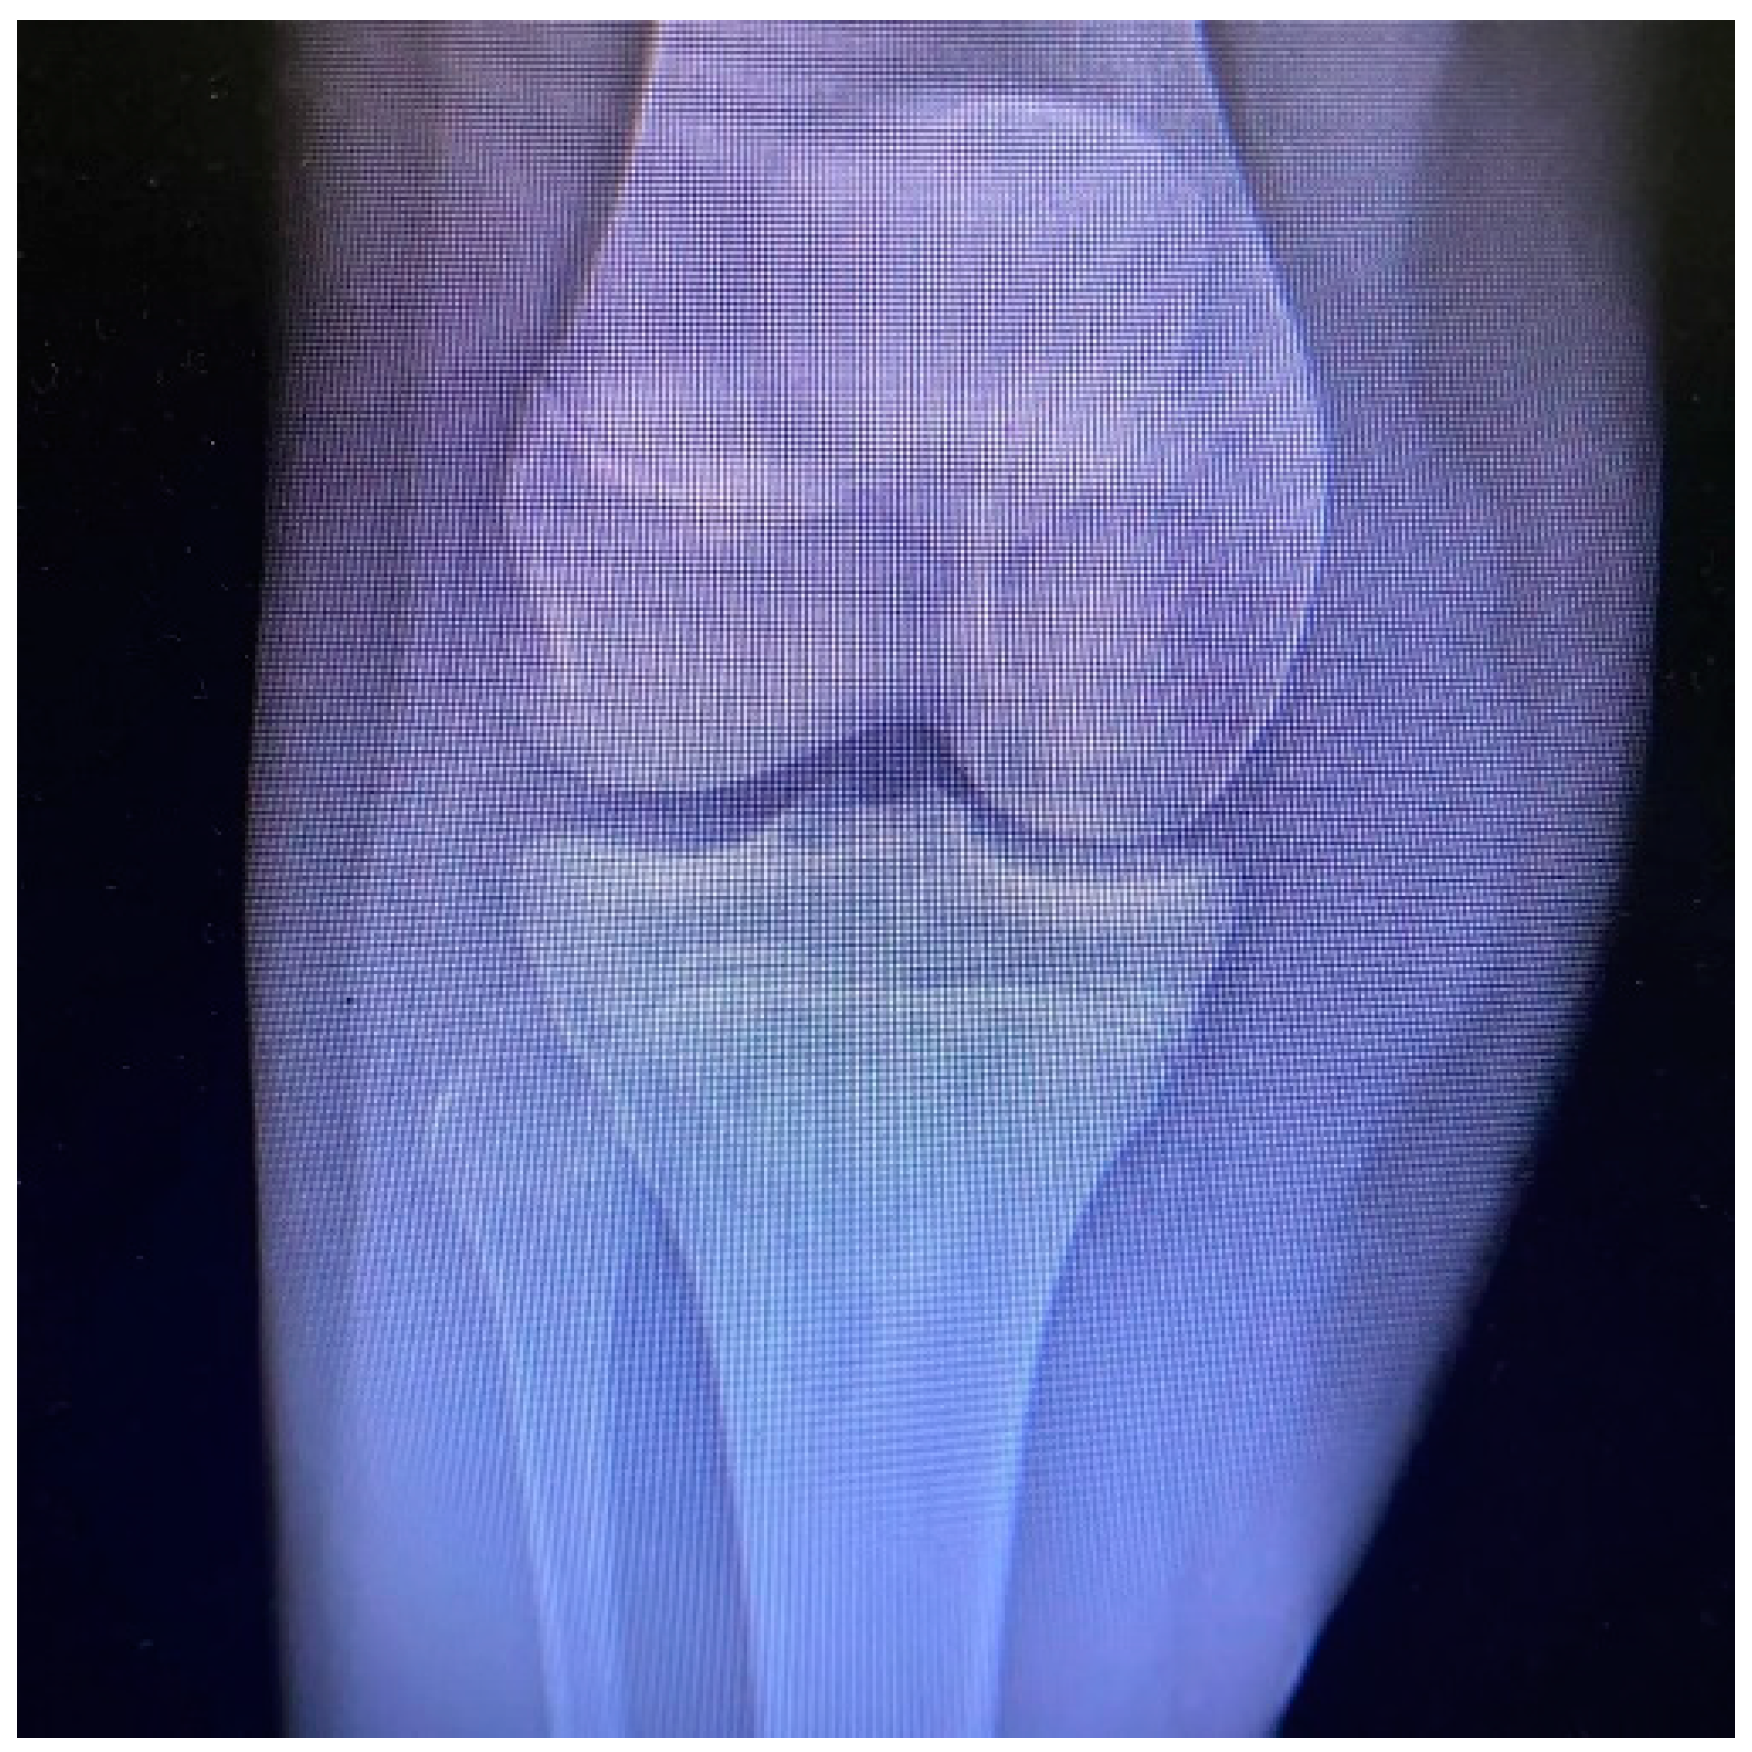

Tibial Tubercle Avulsion Fracture in Young Athletes Surgically Treated: Mid-Long Term Result and Comparison

2. Materials and Methods

2.3. Surgical Treatment and Complications